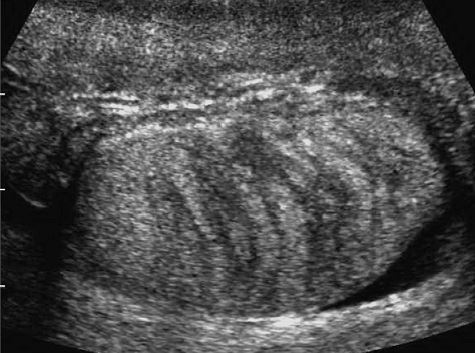

Focal testicular atrophy

• Focal hypoechoic striations and bandlike regions radiating from the periphery of the testis toward the mediastinum.

• Due to focal tubular atrophy and fibrosis